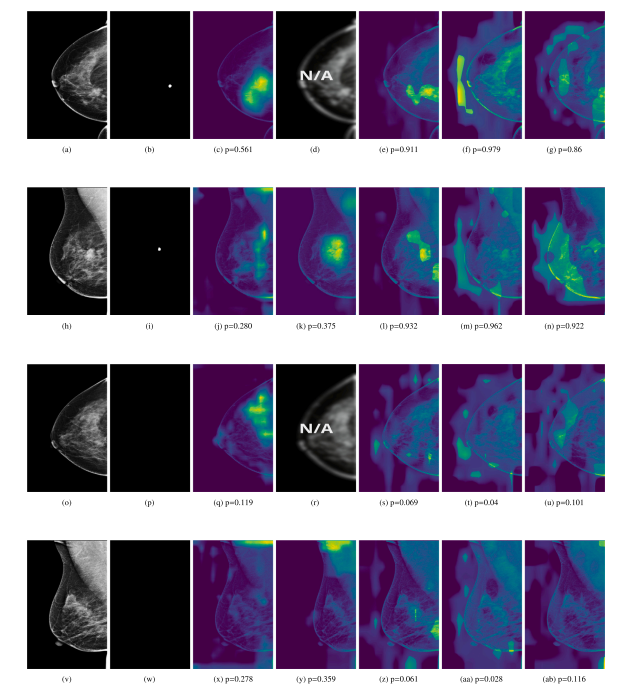

Fig. 16. Grad-CAM heatmap for the cancer prediction task. From left to right, each row displays the original image, the corresponding lesion annotation mask, and the GRADCAMsobtained from the Baseline, AGN4V and MaMVT-(v1 Imagenet, v1 PEAC and v2) architectures along with the corresponding prediction score. While the GRADCAM for the baselineand AGN4V architectures are more focused on local areas, the MaMVT architectures attend to larger portion of the breast parenchyma independently of the prediction score.

图16. 癌症预测任务的Grad-CAM热图。从左到右,每行依次显示原始图像、相应的病灶标注掩膜,以及从Baseline、AGN4V和MaMVT(v1 Imagenet、v1 PEAC和v2)架构中获得的GRADCAM热图及相应的预测评分。与Baseline和AGN4V架构的GRADCAM热图更集中于局部区域相比,MaMVT架构的热图无论预测评分如何,都会关注到更大范围的乳腺实质。

Fig. 17. Grad-CAM heatmap for the cancer prediction task on different views of the same exam. From top to bottom, each column displays the L-CC, L-MLO, R-CC and R-MLO.From left to right, each row displays the original view image, the corresponding lesion annotation mask, and the GRADCAMs obtained from the Baseline, AGN4V (when possible)and MaMVT-(v1 Imagenet, v1 PEAC and v2) architectures along with the corresponding prediction score. While the GRADCAM for the baseline and AGN4V architectures are more focused on local areas, the MaMVT architectures attend to larger portion of the breast parenchyma independently of the prediction score.

图17. 不同视图下的同一检查中的癌症预测任务的Grad-CAM热图。从上到下,每列依次显示L-CC、L-MLO、R-CC和R-MLO视图。从左到右,每行依次显示原始视图图像、相应的病灶标注掩膜,以及从Baseline、AGN4V(如果适用)和MaMVT(v1 Imagenet、v1 PEAC和v2)架构中获得的GRADCAM热图及相应的预测评分。与Baseline和AGN4V架构的GRADCAM热图更集中于局部区域相比,MaMVT架构的热图无论预测评分如何,都会关注到更大范围的乳腺实质